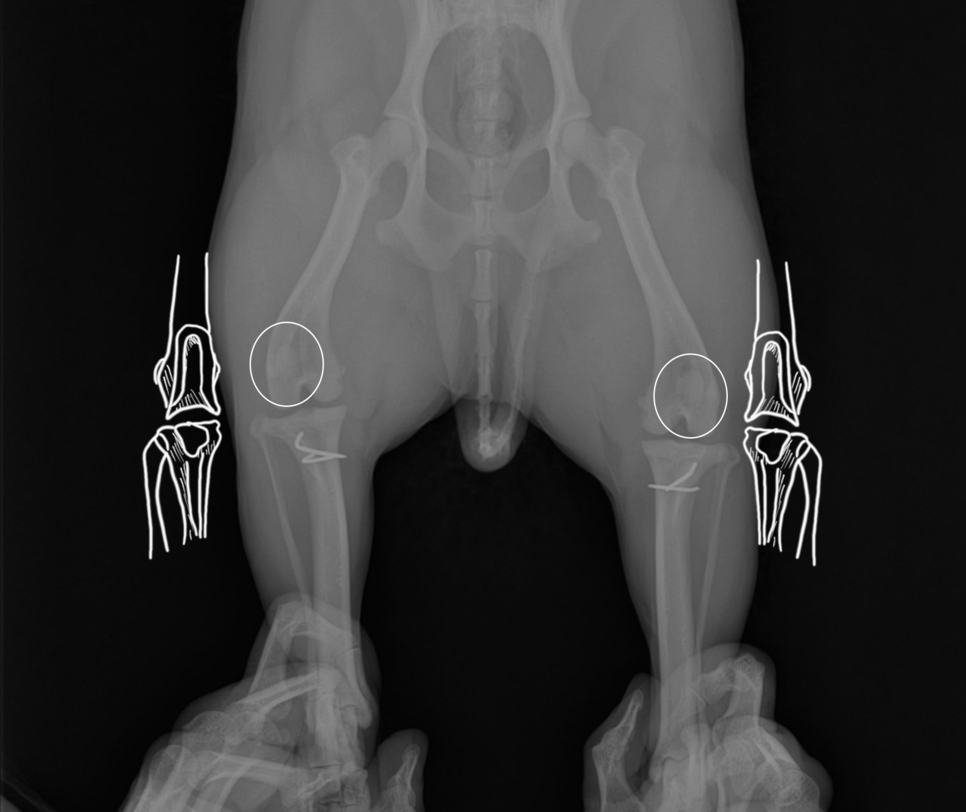

오른쪽 다리도 왼쪽 다리와 마찬가지로 활차 구성형술과 지대중첩,경골조면변위술이 진행되었습니다.

양측 슬개골 수술이 끝난 사진

환자는 수술한 날짜는 다르나, 결과적으로 양측 슬개골을 모두 수술하게 되었고, 큰 이상 없이 퇴원하였습니다.

그 이후 내원하여 진행한 보행 평가와 방사선 검사도 문제없이 치료 종료되었습니다.

활차구 성형술로 고랑을 깊게 파 준 사진